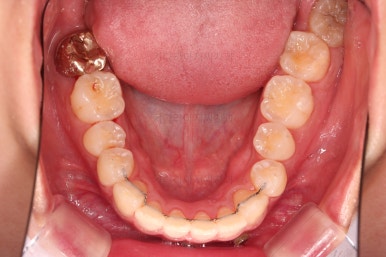

초진 시 입안의 모습입니다.

어금니 쪽은 약간 삐뚤긴 하지만 꼭 교정해야 할 정도는 아니고, 불편감 없이 비교적 잘 맞물리는 상태였습니다.

다만, 앞니ㅉㄱ이 공간이 부족해서 중간 치아들이 많이 회전되어있는데, 이를 환자분들의 표현에 따르면 "나비치아" 라고 부릅니다.

위아래 중간 앞니가 모두 나비치아처럼 되어있고요.

윗니가 아랫니보다 앞쪽으로 나와 있는 모습에 아래앞니가 윗니쪽으로 깊숙이 올라간 "과개교합" 양상을 보였습니다.